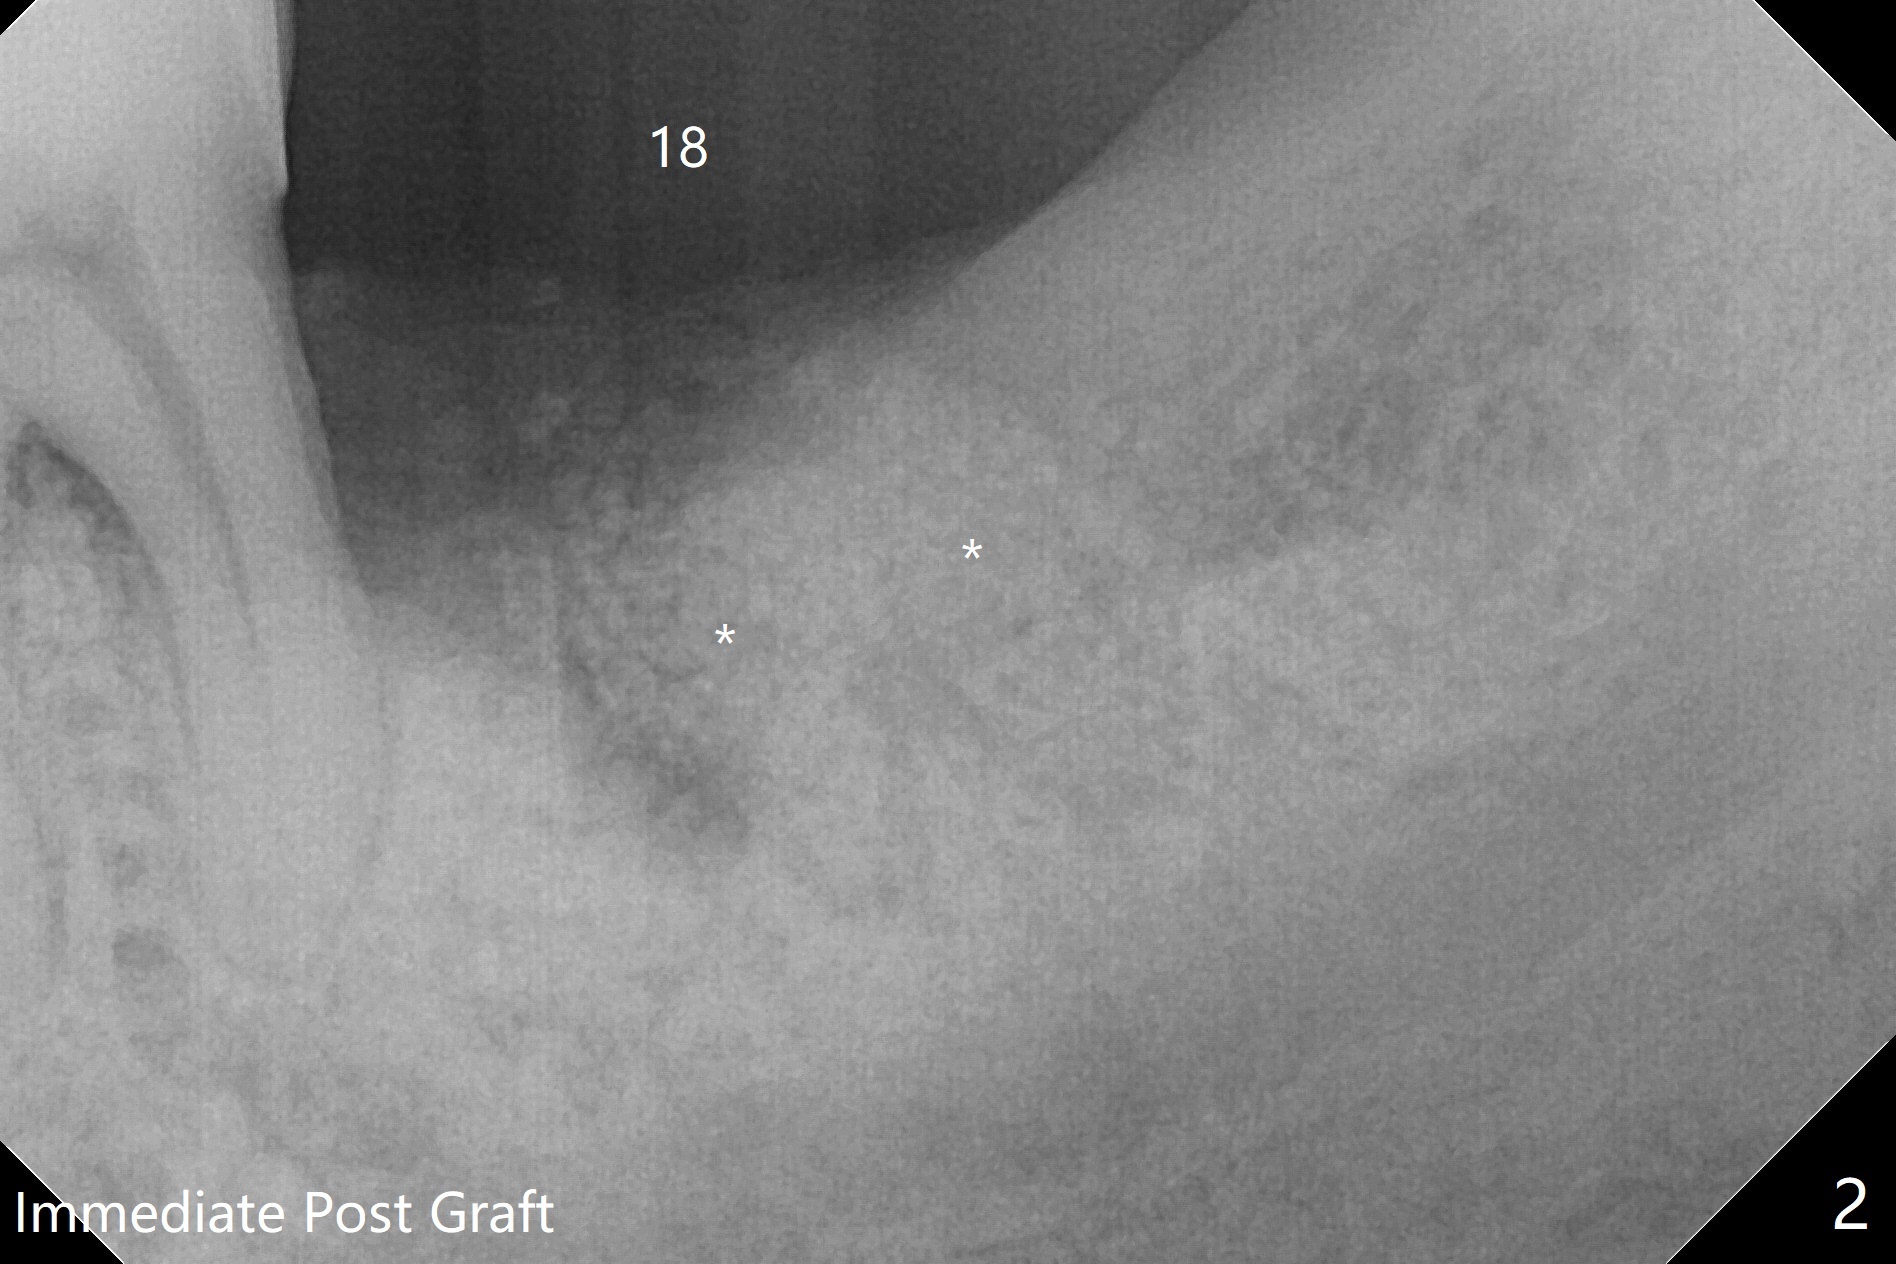

病人舌头大,取模时19号牙舌侧不全(图三),导板制作就没有覆盖舌侧(图四),导板向舌侧倾斜,不准确,植牙就太偏颊侧(图一)。取出植体还必须做近中颊侧切口,放置粘性骨粉和PRF膜(图二:*),PGA缝合,牙周胶水。